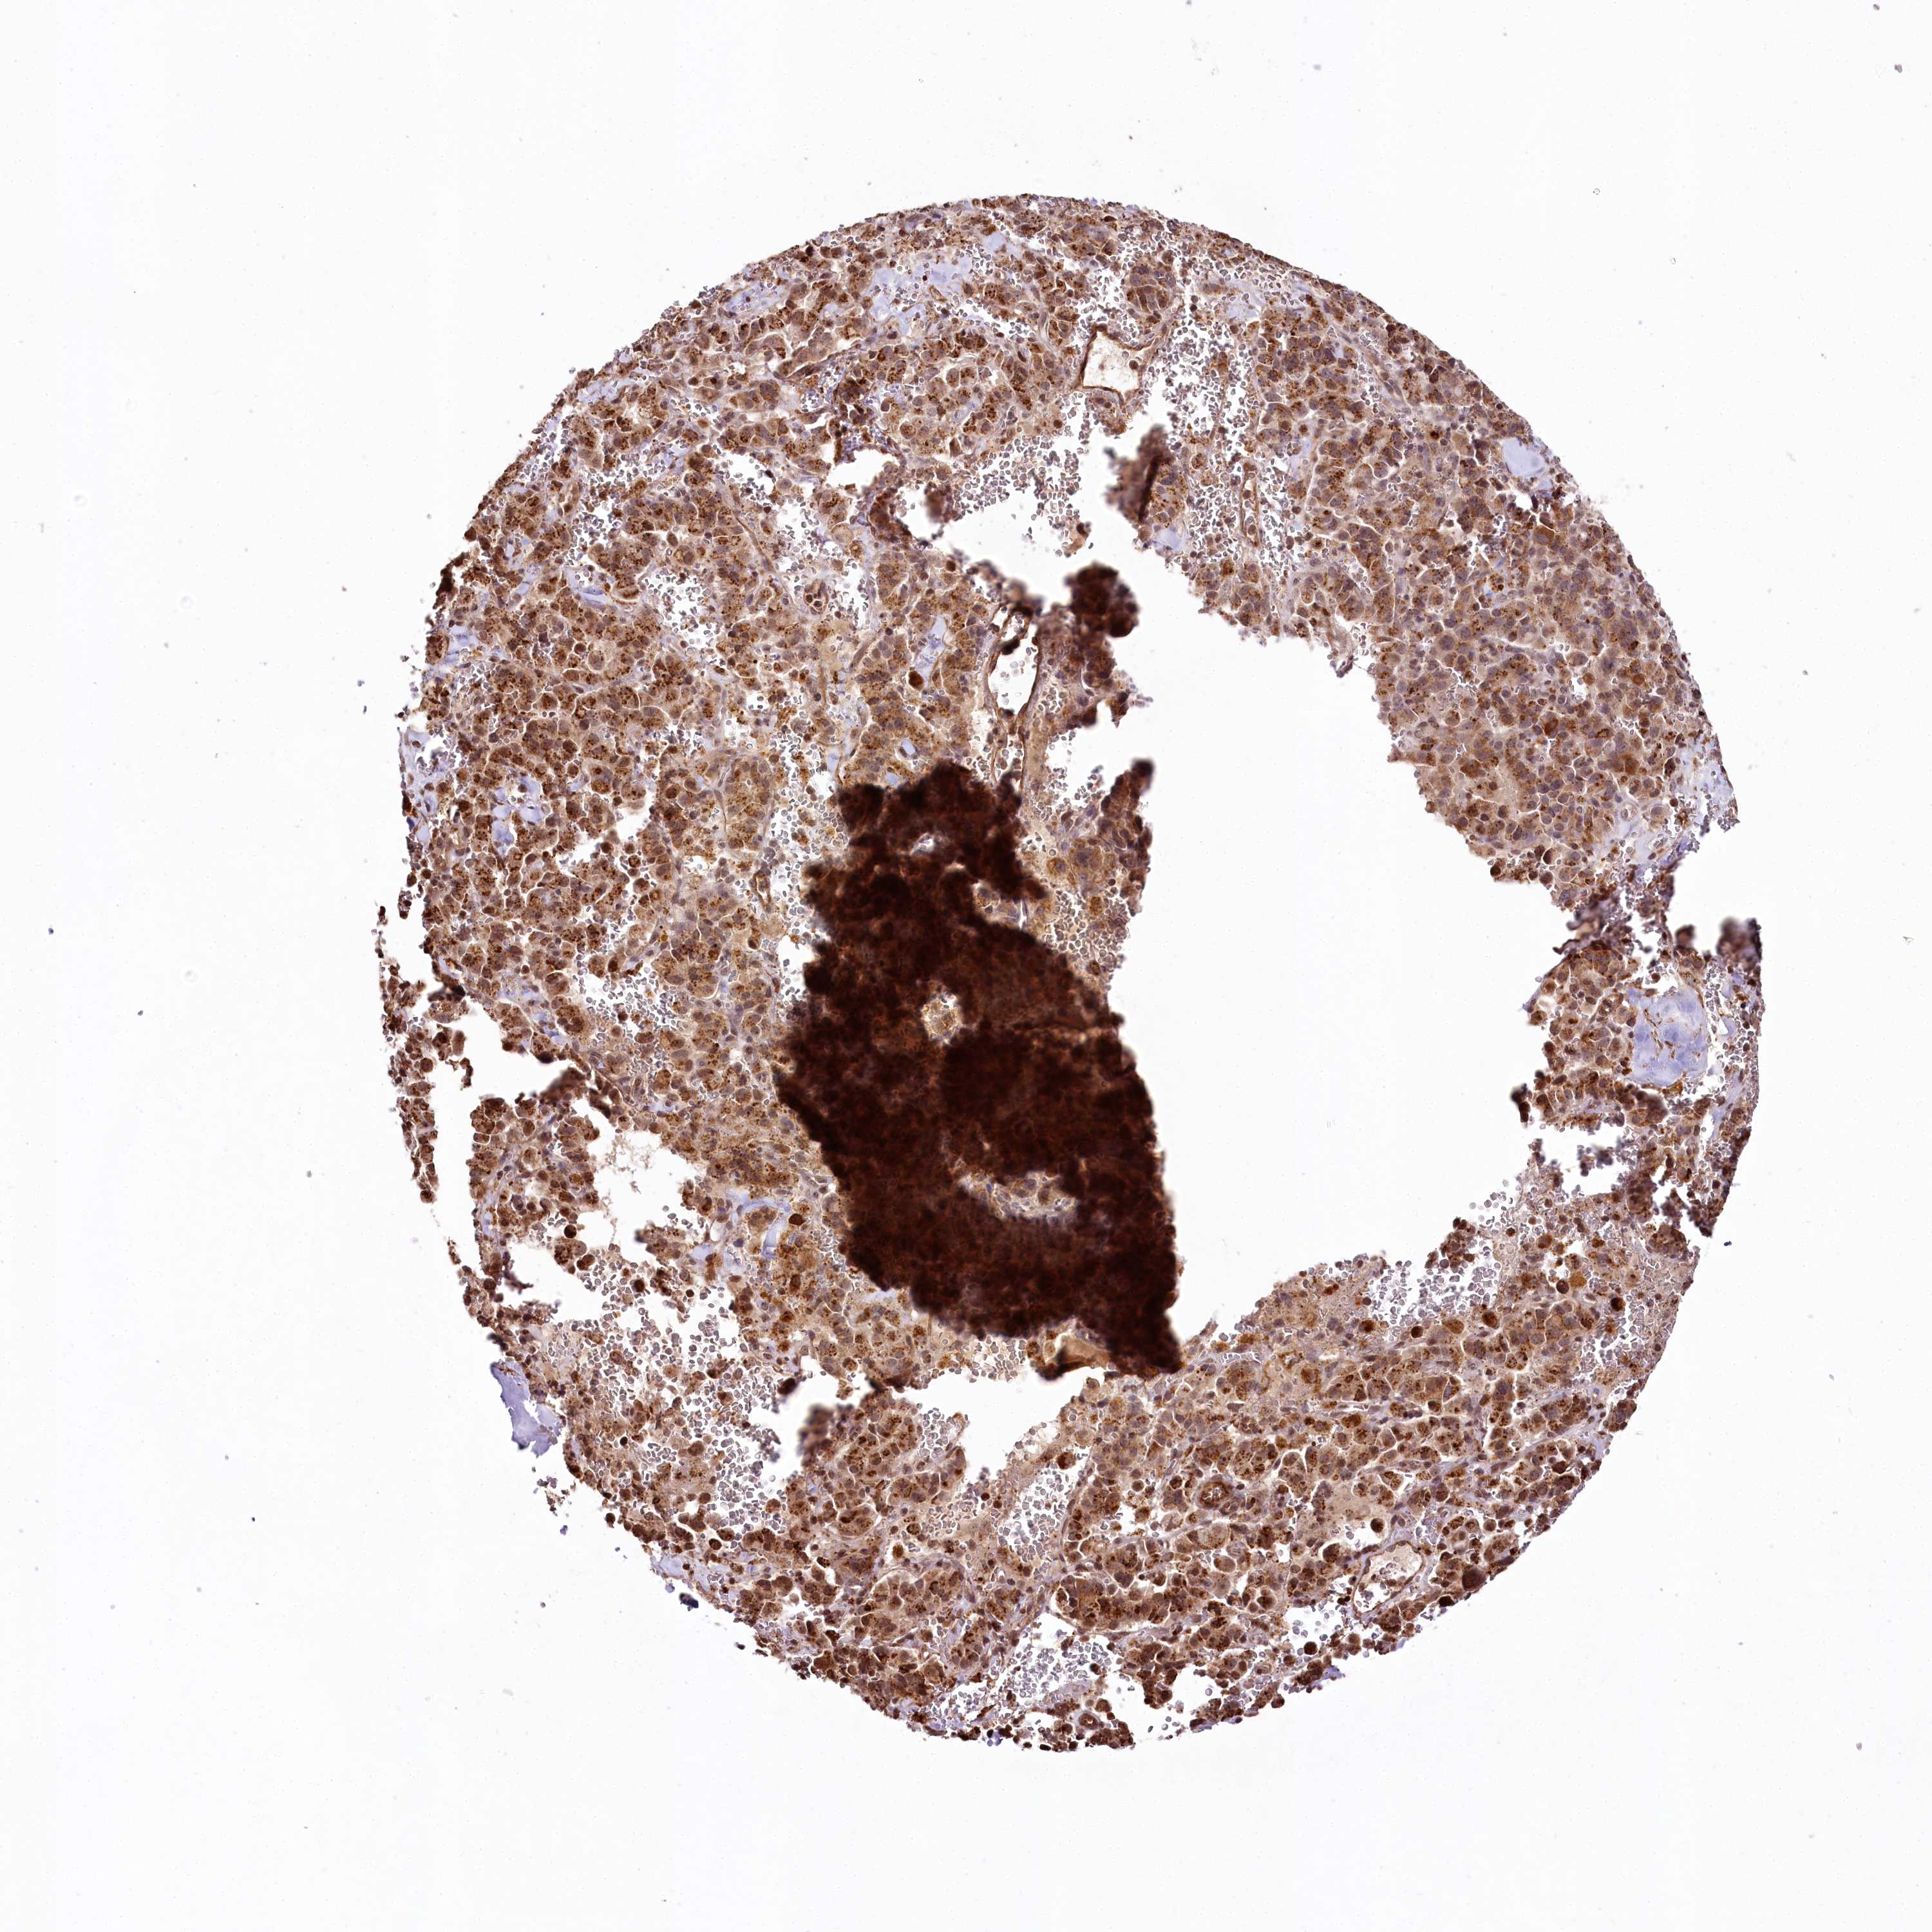

PANCREATIC CANCER - Protein expressioni

A mouse-over function shows sample information and annotation data. Click on an image to view it in a full screen mode. Samples can be filtered based on level of antibody staining by selecting one or several of the following categories: high, medium, low and not detected. The assay and annotation is described here.

Note that samples used for immunohistochemistry by the Human Protein Atlas do not correspond to samples in the TCGA dataset.

Antibody stainingi

Antibody staining in the annotated cell types in the current human tissue is reported as not detected, low, medium, or high, based on conventional immunohistochemistry profiling in selected tissues. This score is based on the combination of the staining intensity and fraction of stained cells.

Each image is clickable and will lead to virtual microscopy that enables deeper exploration of all samples and also displays staining intensity scores, fraction scores and subcellular localization as well as patient and tissue information for each sample.

Antibody HPA028911

Antibody CAB037020

Staining

High

Medium

Low

Not detected

Intensity

Strong

Moderate

Weak

Negative

Quantity

>75%

75%-25%

<25%

None

Location

Nuclear

Cytoplasmic/membranous

Cytoplasmic/membranous,nuclear

Adenocarcinoma, NOS